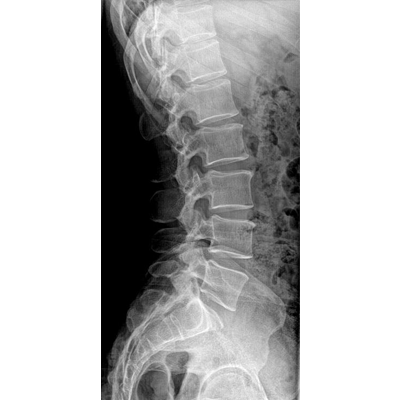

●探測器可以大范圍轉(zhuǎn)動,大尺寸有效探測面積,可滿足人體多部位攝影需求。